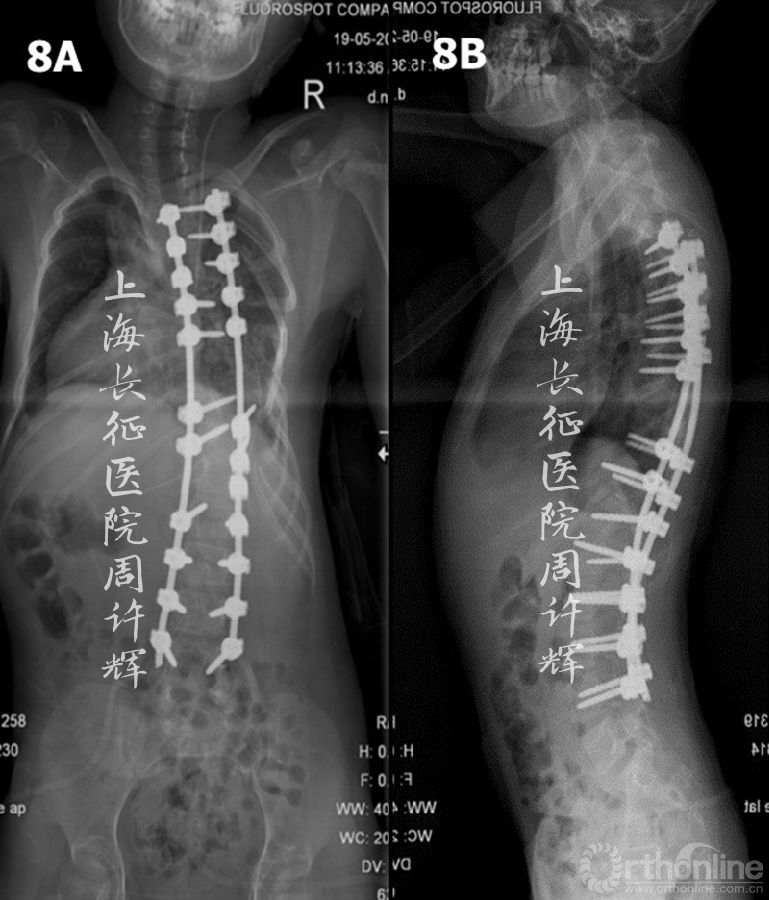

全麻下胸7-8VCR+三维矫形内固定术。术后矫形效果满意(图8)。